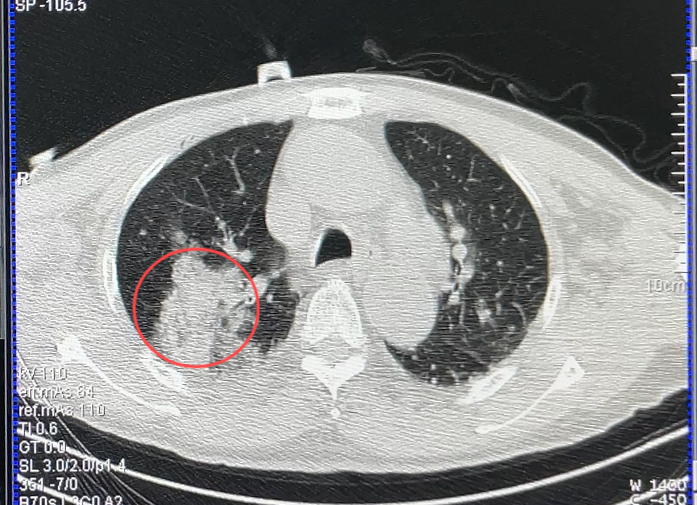

2月21日,贵州航天医院国务院政府特殊津贴专家、二级教授、学科带头人廖江荣教授呼吸团队再次为一名81岁的患者成功实施AI机器人辅助经皮穿刺氩氦刀冷冻消融术,仅用40分钟就完成对肺结节的“精准狙击”。 “AI机器人不仅提供高精度的穿刺方案,还能通过机械臂稳定执行,避免人工操作的手部震颤误差。”廖江荣教授介绍。 传统经皮穿刺氩氦刀冷冻消融术高度依赖医生经验,面对复杂病灶时,常面临“定位难、穿刺深、耗时长”的挑战。在此次手术中,呼吸团队借助AI机器人智能影像分析、穿刺计划系统,对患者肺结节进行了多视角的立体三维重建,精确定位了病灶,并规划出最佳进针位置、角度和轨迹,通过AI机器人可视影像系统和机械臂穿刺系统的引导,“一针”就穿刺进入病灶预定位置进行冷冻消融,手术过程仅40分钟。 术 前 机器人机械臂定位中 完成定位 消融针通过机械臂导引孔精准到达病灶位置 冷冻消融中 消融后,晕征范围完全覆盖结节位置 此次接受手术的是一位81岁的高龄患者,肺结节最大径达2.3cm,由于身体条件限制,传统手术风险较高,在AI机器人辅助下的氩氦刀冷冻消融术完成了病灶的精准消融。 什么是AI机器人辅助消融治疗? AI机器人辅助消融治疗术是一种较为先进精准、微创的技术,医生通过AI机器人精密的操作系统,以毫米级的精确度操控冷冻或微波探针,直达靶点,释放低温或高温摧毁病变组织,同时明显提升了手术的安全性和效率。 与外科手术相比,消融治疗的创伤程度要轻许多,极大地减轻了患者的手术痛苦,缩短了康复周期。 与徒手穿刺相比,AI机器人规划和辅助引导定位具有更稳定、更精准、更安全的优势,避免反复调整穿刺方向与深度,造成更多的伤害。 如果病灶靠近肺内大的血管、气管或肺外的重要脏器,AI机器人辅助消融能最大限度避开高危部位,保护周围健康肺组织不受损伤。 什么是氩氦刀冷冻消融? 氩氦刀冷冻消融是通过将一根1.7-3毫米的中空钢针,穿刺进入病灶,先注入氩气,迅速降温至-160摄氏度,冰冻肿瘤数分钟,再注入氦气,快速升温至20-30摄氏度,共历经3个冷冻、复温循环过程,对病灶组织进行物理性杀灭。 主要适用于 2.重要脏器功能不全,体质过弱,不宜手术的患者。 3.术后复发、转移性癌灶、多发癌灶的患者。 4.晚期患者延长生命提高生存质量的姑息性治疗。 5.因各种原因拒绝手术的患者。 贵州航天医院呼吸与危重症医学科微创介入诊疗技术已达到国内前列,省内领先水平,是亚洲冷冻治疗学会常务理事单位,并获批成立遵义市肺结节多学科(MDT)微创诊疗中心。 肺结节MDT门诊出诊信息 出诊时间: 周一至周五 8:00--12:00;14:00--17:00 出诊地点: 遵义市肺结节多学科微创诊疗中心(MDT)门诊(贵州航天医院呼吸综合楼1楼) 呼吸与危重症医学科与心胸外科、医学影像科、麻醉科等科室建立了多学科(MDT)会诊机制,结合患者情况,通过采取外科手术、冷、热消融等多种治疗手段,帮助患者安全、有效、精准、科学、快速治疗肺结节,单次消融手术时间约半小时左右,几乎没有疼痛,且并发症少,3-5天即可出院,有效减少了患者因开刀手术需长时间恢复的痛苦。 注:图片来源于网络,如有侵权,请联系删除。 贵州航天医院 呼吸与危重症医学科专家团队 廖江荣 国务院政府特殊津贴专家 二级教授 主任医师 呼吸与危重症医学科 学科带头人 国家级学术任职: 第二届中国医药教育协会介入微创专业委员会呼吸分会副主任委员 中国抗癌协会肿瘤微创治疗专业委员会常务委员 中国防痨协会结核病转化医学专业分会常务委员 第一届中国人体健康科技促进会呼吸介入专委会常务委员 中国医疗保健国际交流促进会结核病学分会第三届委员会常务委员 中国抗癌协会肿瘤微创治疗专业委员会粒子治疗学组第四届委员会委员 中华医学会结核临床专业委员会内镜介入委员 中华医学会放射学分会第十五届委员会介入学组呼吸系统介入专业委员会委员 北京健康促进会中青年专家委员会胸部疾病精准活检分委会副主任委员 中国医师协会介入医师分会第二届委员会肿瘤消融专业委员会委员 中国结核病防治综合质量控制专家指导委员会委员 亚洲冷冻治疗学会常务委员 世界内镜医师协会呼吸内镜协会常务理事 内镜临床诊疗质量评价专家委员会委员 “西部呼吸介入联盟”副理事长 专业擅长: 呼吸系统(肺)疑难病的诊断及危重病的抢救,呼吸系统(肺)感染性、疑难性疾病介入快速诊断(ROSE),尤其在肺癌、肺小结节早期诊断,肺癌微创综合靶向治疗,难治性、复治性、重症肺结核诊疗,硬质支气管下复杂性气道狭窄诊治,纤支镜介入治疗气道肿瘤、结核、气道狭窄(球囊扩张、支架植入、高频电刀、氩气刀、冷冻、灌洗、注药、微波消融),间质性肺疾病的诊疗上具有极高水平;带领团队勇于创新,在贵州省率先开展多项新技术、新疗法,如CT引导下及纤支镜下I125粒子植入及CT引导下微波、射频消融介入治疗肺癌等多项新技术,带动了贵州省肺部疾病的介入治疗水平提高。 蒋 婷 呼吸与危重症医学科 总负责人 副主任医师 专业擅长:从医20余年,在呼吸系统疾病、介入呼吸病学、肺部结核、肺部肿瘤等方面具有丰富的临床经验和专业技能,尤其是慢性阻塞性肺疾病、支气管扩张、肺结核、耐药肺结核、肺癌、胸腔积液等肺部疾病的诊治、微创介入、危重病患者抢救。 现任中国防痨协会人兽共患结核病专业分会委员,中国女医师协会第一届介入专业委员会委员,贵州省基层呼吸疾病防治联盟-间质性肺疾病联盟委员,贵州省防痨协会第七届理事会理事,贵州省中西医结合学会呼吸专业委员介入呼吸病学组委员,贵州省遵义市中医药学会中西医结合肺病(呼吸)分会副主任委员,贵州省遵义市中医药学会中医肿瘤专业委员会常委;发表论文数篇,参与并主持多项科研项目。 李桂凤 呼吸与危重症医学科 三病区 主任 副主任医师 专业擅长:从事呼吸系统疾病、结核病学、介入呼吸病学、肿瘤综合治疗、呼吸康复等临床工作20余年,擅长呼吸内科常见病、多发病及疑难重症危重病症的诊治,尤其对重症疑难结核及耐药结核病、介入治疗(肺)呼吸系统疾病、呼吸危重病抢救等方面具有较高诊疗水平。 中国防痨协会非结核病专业委员会委员,贵州省中西医结合学会第六届呼吸专业委员会委员,贵州省康复学会睡眠障碍康复专业委员会委员,遵义市呼吸内科医疗质量控制中心委员,遵义市落实民生实事结核病筛查阅片专家组成员;主持及参与实用新型专利3项。 周裕祥 呼吸与危重症医学科 四病区 主任 副主任医师 专业擅长:经皮肺介入、经血管介入诊疗技术。 贵州省中西医结合学会呼吸专业委员会介入呼吸病学组常务委员,中国医师协会呼吸医师分会介入呼吸病学工作委员会呼吸病血管介入学组委员,贵州省中西医结合学会呼吸学分会委员,遵义市医学会放射肿瘤治疗学分会委员,中国医药教育协会介入微创呼吸分会委员,北京健康促进会中青年专家委员会胸部疾病精准活检分委会委员;曾赴重庆医科大学RICU、珠海市人民医院介入科进修学习。 杨 芳 呼吸与危重症医学科 内镜中心 主任 副主任医师 专业擅长:从事临床工作约16年,对呼吸危重病的救治有独到的见解,尤其擅长呼吸系统疾病的介入诊疗,对呼吸内镜下的诊治及经皮肺穿刺诊疗技术具有丰富的临床经验。 亚洲冷冻治疗学会委员,中国医药教育协会介入微创呼吸分会委员,西南结核病医院联盟第二届委员会秘书/委员,贵州省中西医结合学会第六届呼吸科专业委员会委员,贵州省中西医结合学会呼吸专业委员会介入呼吸病学组秘书,贵州省中西医结合学会呼吸专业委员会基层康复学组副组长,贵州水利电力医学科学技术会高原医学分会委员,遵义市中医院学会中西医结合肺病(呼吸)分会秘书/常务委员,遵义市医学会肿瘤学分会(第二届)委员,遵义市医学会放射肿瘤治疗学分会第二届委员;主持及参与科研课题多项,参编著作《呼吸内镜操作技术规范》、《介入结核病学》,发表论文数篇。 贵州航天医院 呼吸与危重症医学科简介 贵州航天医院呼吸与危重症医学科以呼吸危重症和介入呼吸病学为强力推手,以肺部感染性疾病及肺癌、肺小结节的早期精准诊疗、慢性呼吸疾病康复治疗为特色,以人才团队建设为核心的科室发展模式,现已成为省内呼吸疾病治疗规模最大,诊疗项目最全的呼吸疾病品牌科室。是贵州省医学重点学科、临床医学重点专科建设单位,遵义市首批呼吸重点学科、重点专科建设单位。是国家卫健委能力建设和继续教育肿瘤微创介入建设中心、贵州省县级医院微创介入培训中心、遵义市呼吸疾病临床医学中心。是国家呼吸医疗质量控制与管理哨点医院、遵义市呼吸内科专业医疗质量控制中心。是中国医药教育协会介入微创呼吸分会呼吸介入技术培训中心单位;国家卫健委海医会呼吸分会ROSE专委会“诊断性介入肺脏病学快速现场评价”培训基地;中国肺癌防治联盟“贵州航天医院肺结节诊治”分中心,中国人体健康科技促进会呼吸介入技术培训基地,贵州省中西医结合会呼吸学分会呼吸介入专委会主委单位。 基本情况 平均每年开展气管镜诊疗约4000例,经皮肺穿刺介入诊疗近千例,开展的项目包括经支气管镜(软、硬)下冷冻、氩气刀、高频电刀、球囊扩张、支架置入、超声内镜诊疗等气道介入诊疗技术,经皮肺穿刺活检及肿瘤消融术(微波、冷冻)、ROSE技术、内科胸腔镜诊疗及经血管介入诊疗技术,且多项呼吸介入诊疗技术在省内处于领先水平。 诊疗范围 致力于呼吸系统感染性、疑难性疾病的介入快速精准诊疗,肺癌与肺小结节早期精准诊疗水平项目提升。 擅长呼吸系统(肺)疑难病的诊断及危重病的救治,尤其在肺癌、肺小结节的早期诊断,肺癌综合靶向治疗,肺结核综合诊疗,肺部疾病的介入诊疗在省内处于前沿水平。 END